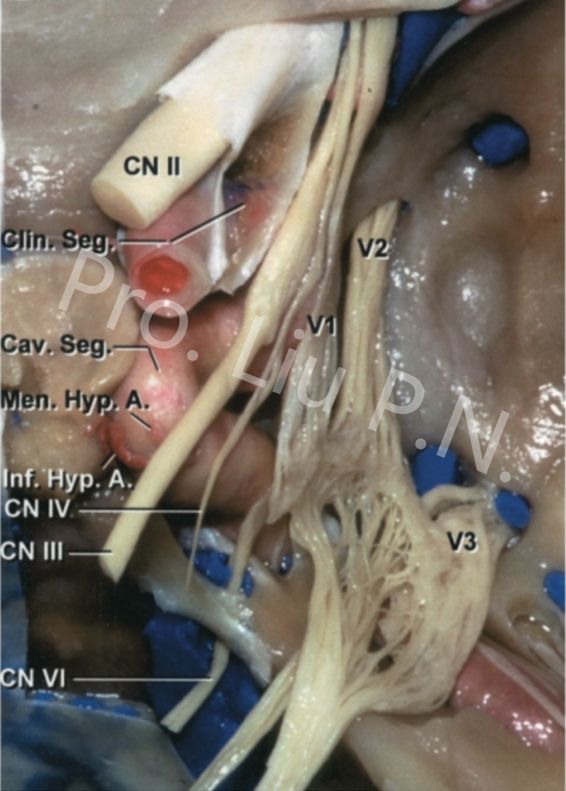

海绵窦是中颅窝底硬膜在鞍旁分层后形成的“扁囊袋”样结构,其外侧壁包裹动眼神经、滑车神经、眼神经、上颌神经及下颌神经。内外侧壁之间有外展神经、颈内动脉海绵窦内段及无瓣膜的静脉丛。

1. 扩大经蝶窦入路:到达海绵窦内侧壁;

2. 经筛-翼突入路:到达海绵窦前壁、内侧壁;

3. 经上颌窦-蝶骨大翼入路:到达海绵窦外侧壁;

4. 经眶外侧壁入路:到达海绵窦外侧壁。